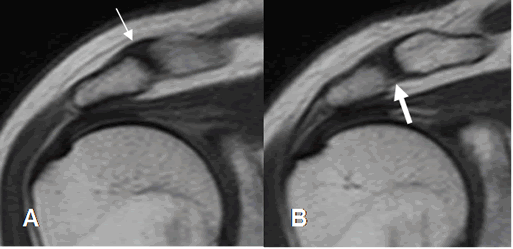

Fig 16. Tendón de la cabeza larga del bíceps normal.

A: RM axial en FFE y B: RM coronal en STIR. Origen del tendón a nivel supraglenoideo y después ocupa la corredera bicipital.